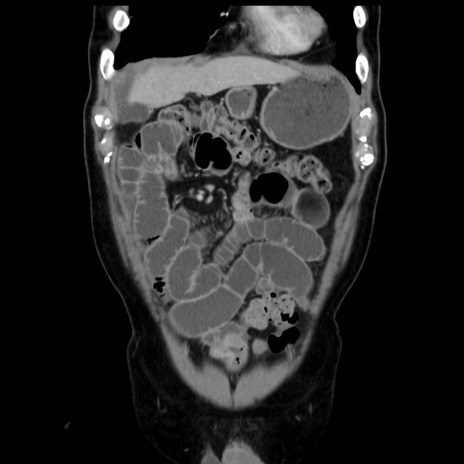

症例16(冠状断像)

【症例】 70歳代男性

【主訴】 腹痛、嘔吐

【現病歴】 約1ヶ月前より間欠的に腹痛と嘔吐あり、当院消化器内科を受診したところCTで多発する肝臓のLDAを指摘され、精査中であった。以降は消化器症状は安定していたが、2日前より嘔気と腹痛があり、同日より排便・排ガスが消失した。改善認めず、 本日、救急外来を受診した。

【既往歴】 大腸ポリープ切除後。

【身体所見】意識清明・会話良好、BT 36.3℃、BP 127/80mmHg、 P 80bpm、腹部:膨満あり、平坦・軟、上腹部正中および下腹部正中に圧痛あり、反跳痛なし、筋性防御なし。

【データ】WBC 7200、CRP 0.77